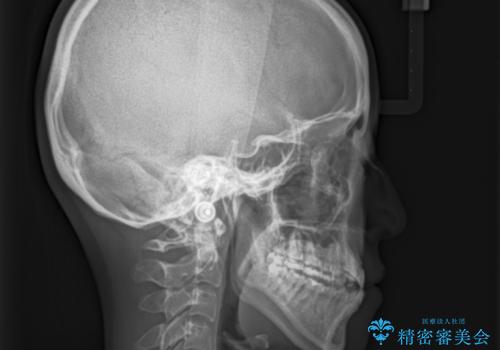

- 治療計画

上顎にTAD(矯正用アンカースクリュー)を設置し、MARPEにより骨格レベルで上顎の幅を拡大。数週間の拡大期間を経て十分なスペースを確保したのち、マウスピース型矯正装置(インビザライン)で歯列全体を整えました。八重歯もアーチ内に自然に収まり、非抜歯で審美性と機能性を両立。治療後は「噛み合わせが安定して笑顔に自信が持てるようになった」とご本人にも大変満足していただきました。